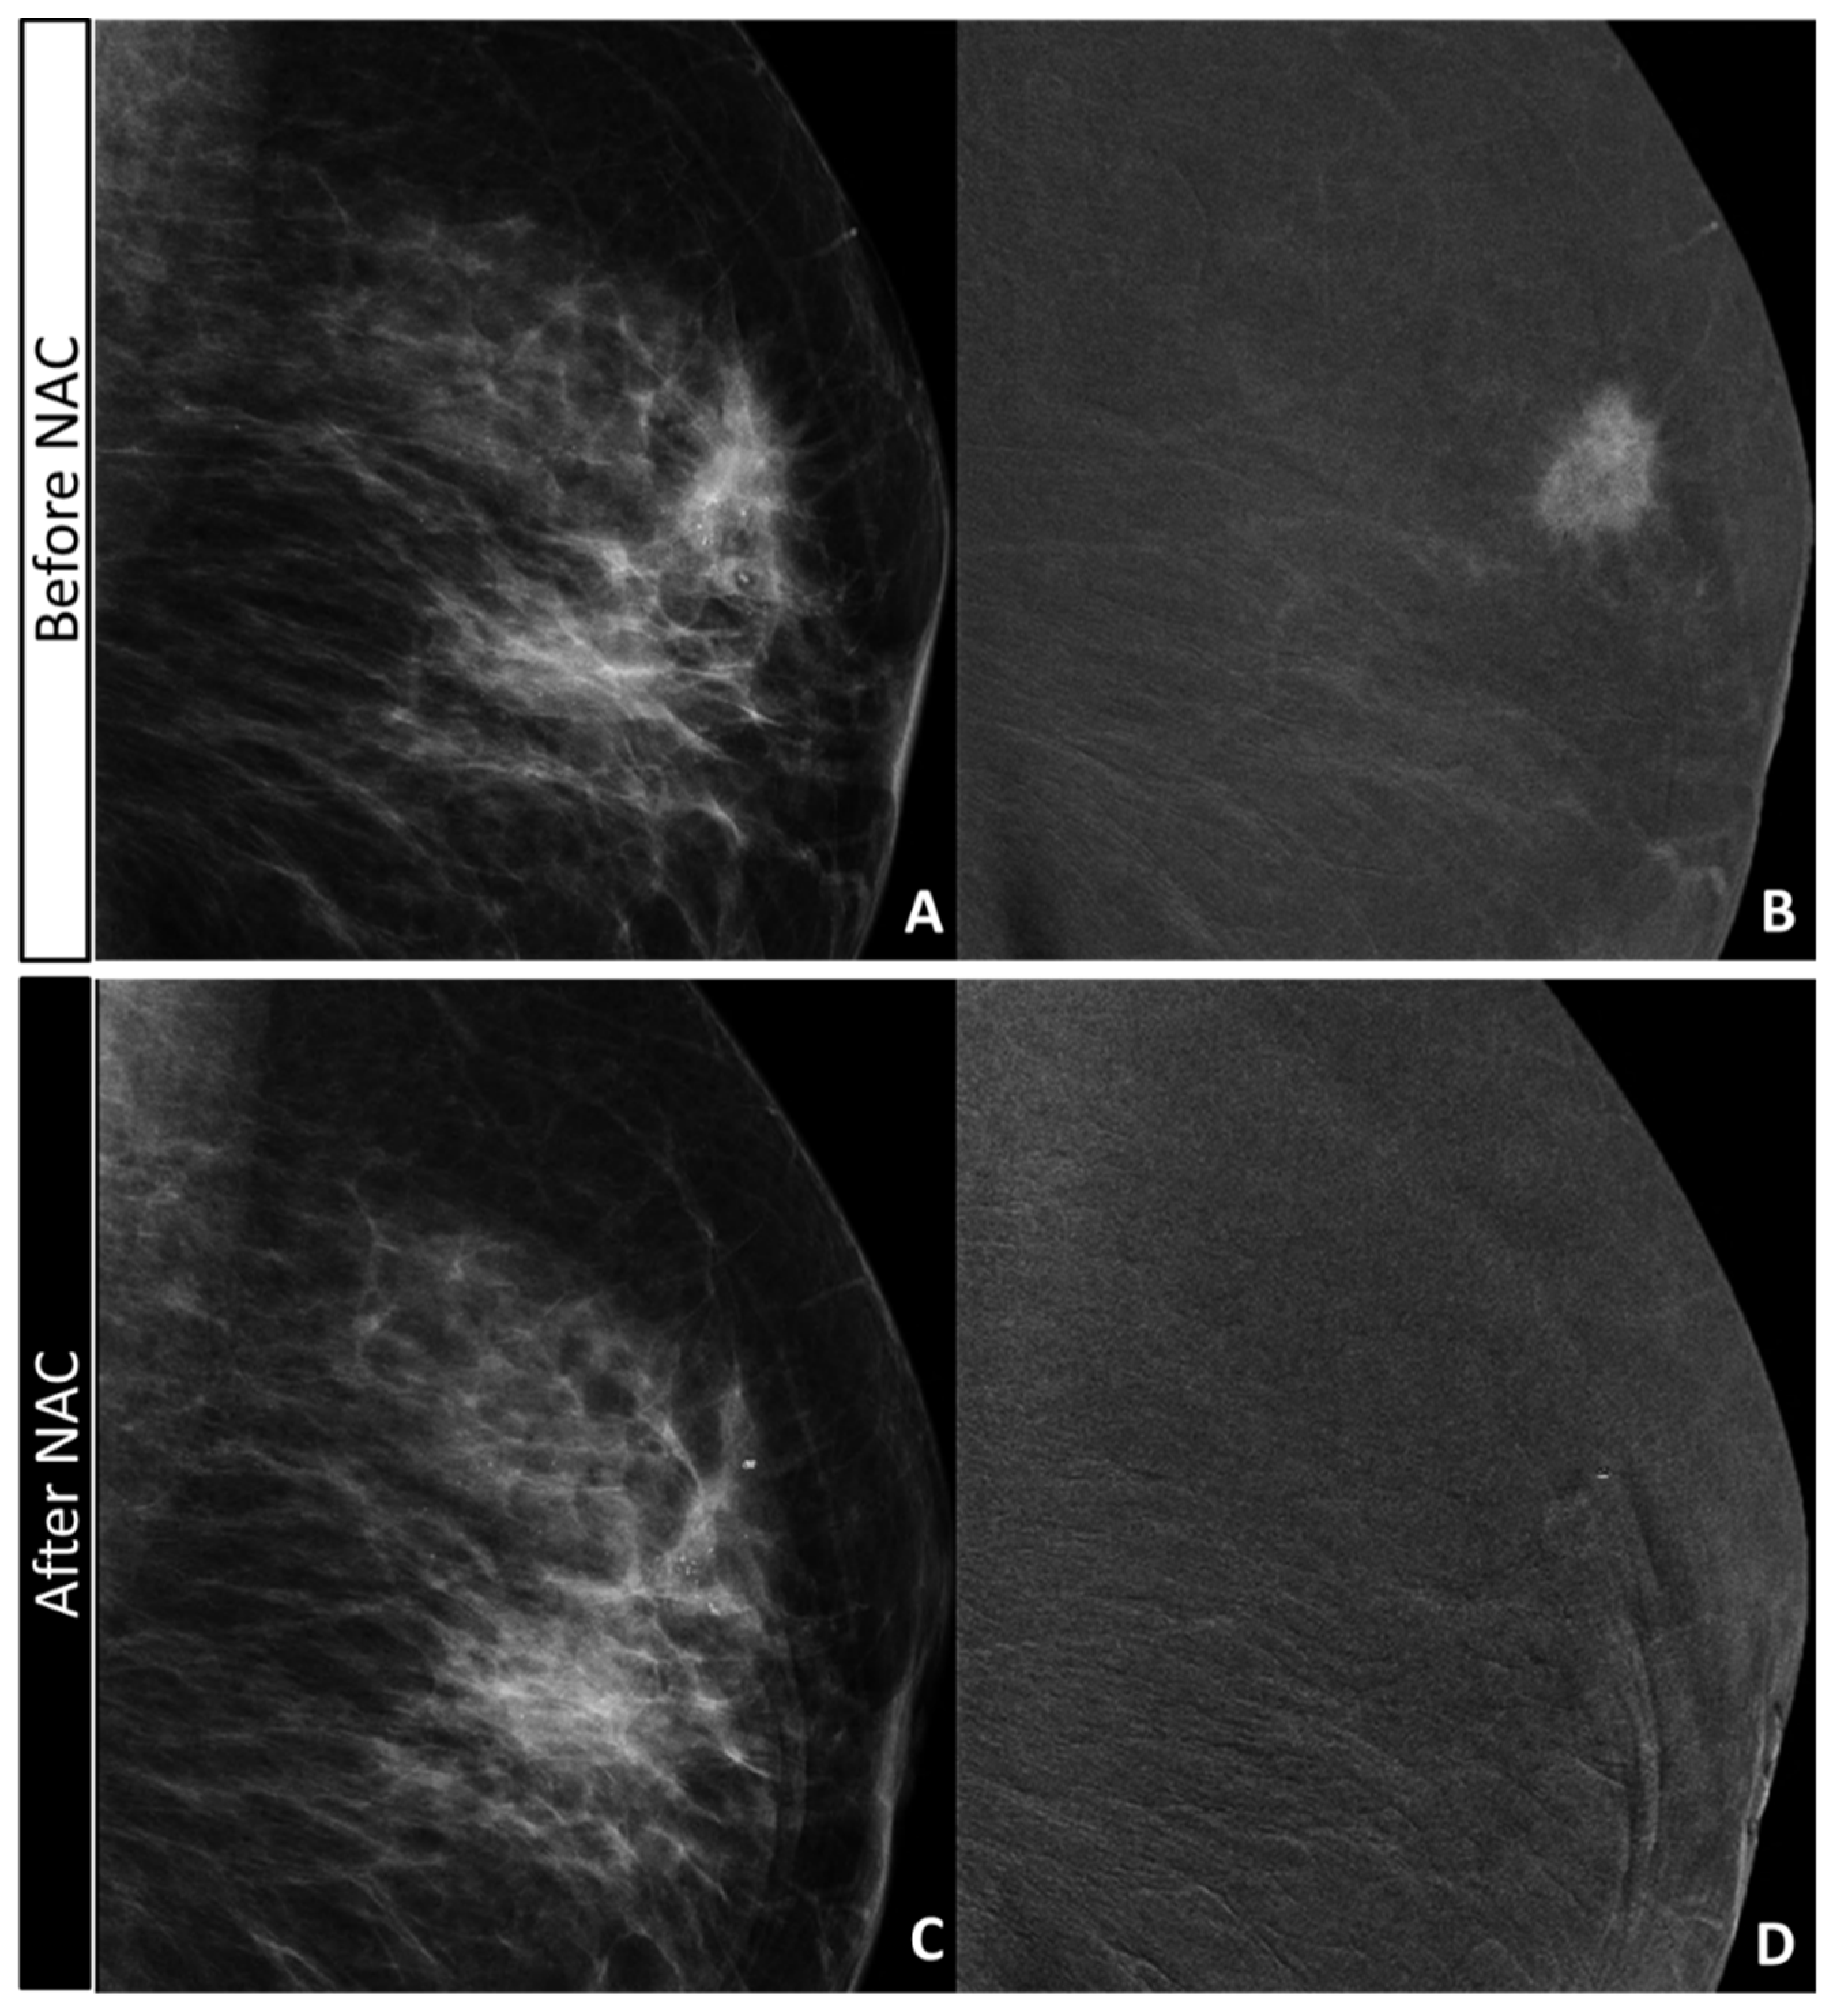

2.4. CEM Image Acquisition and Retrospective Review

- the absence or presence of contrast enhancement (CE) on recombined images, defining the maximum dimension (mm) of CE before NAC (defining the tumor bed) and after NAC (defining the residual disease);

- the maximum extension (mm) and characteristics (according to BIRADS lexicon) of calcifications on low-energy images before NAC (defining the tumor bed) and after NAC (defining the residual disease);

- the maximum extension (mm) of the combined evaluation of pathological calcifications and enhancement before (defining the tumor bed) and after (defining the residual disease) NAC;